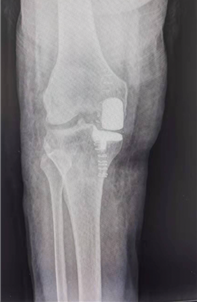

田女士接受UKA手术后的X线片,磨损的内侧间室已经完全被修补替代。